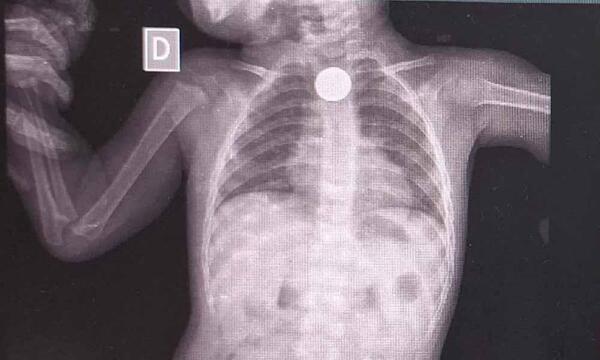

Médicos extrajeron de manera exitosa una moneda del cuerpo de un niño de 1 año en el Hospital General de Coronel Oviedo. Es la primera vez que se realiza este tipo de intervención en el Departamento de Caaguazú. La exitosa extracción de una moneda del cuerpo de un niño se realizó este jueves, la primera […] ...[Leer más]